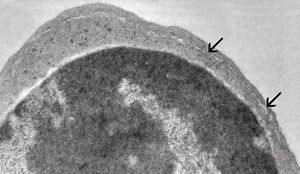

M,33y. | blood - hairy cell leukemia- ribosome-lamella complexin tricholeukocyte